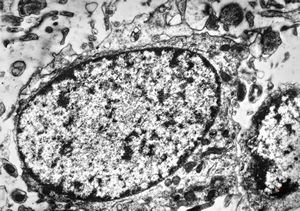

M,10y. | herpetic encephalitis